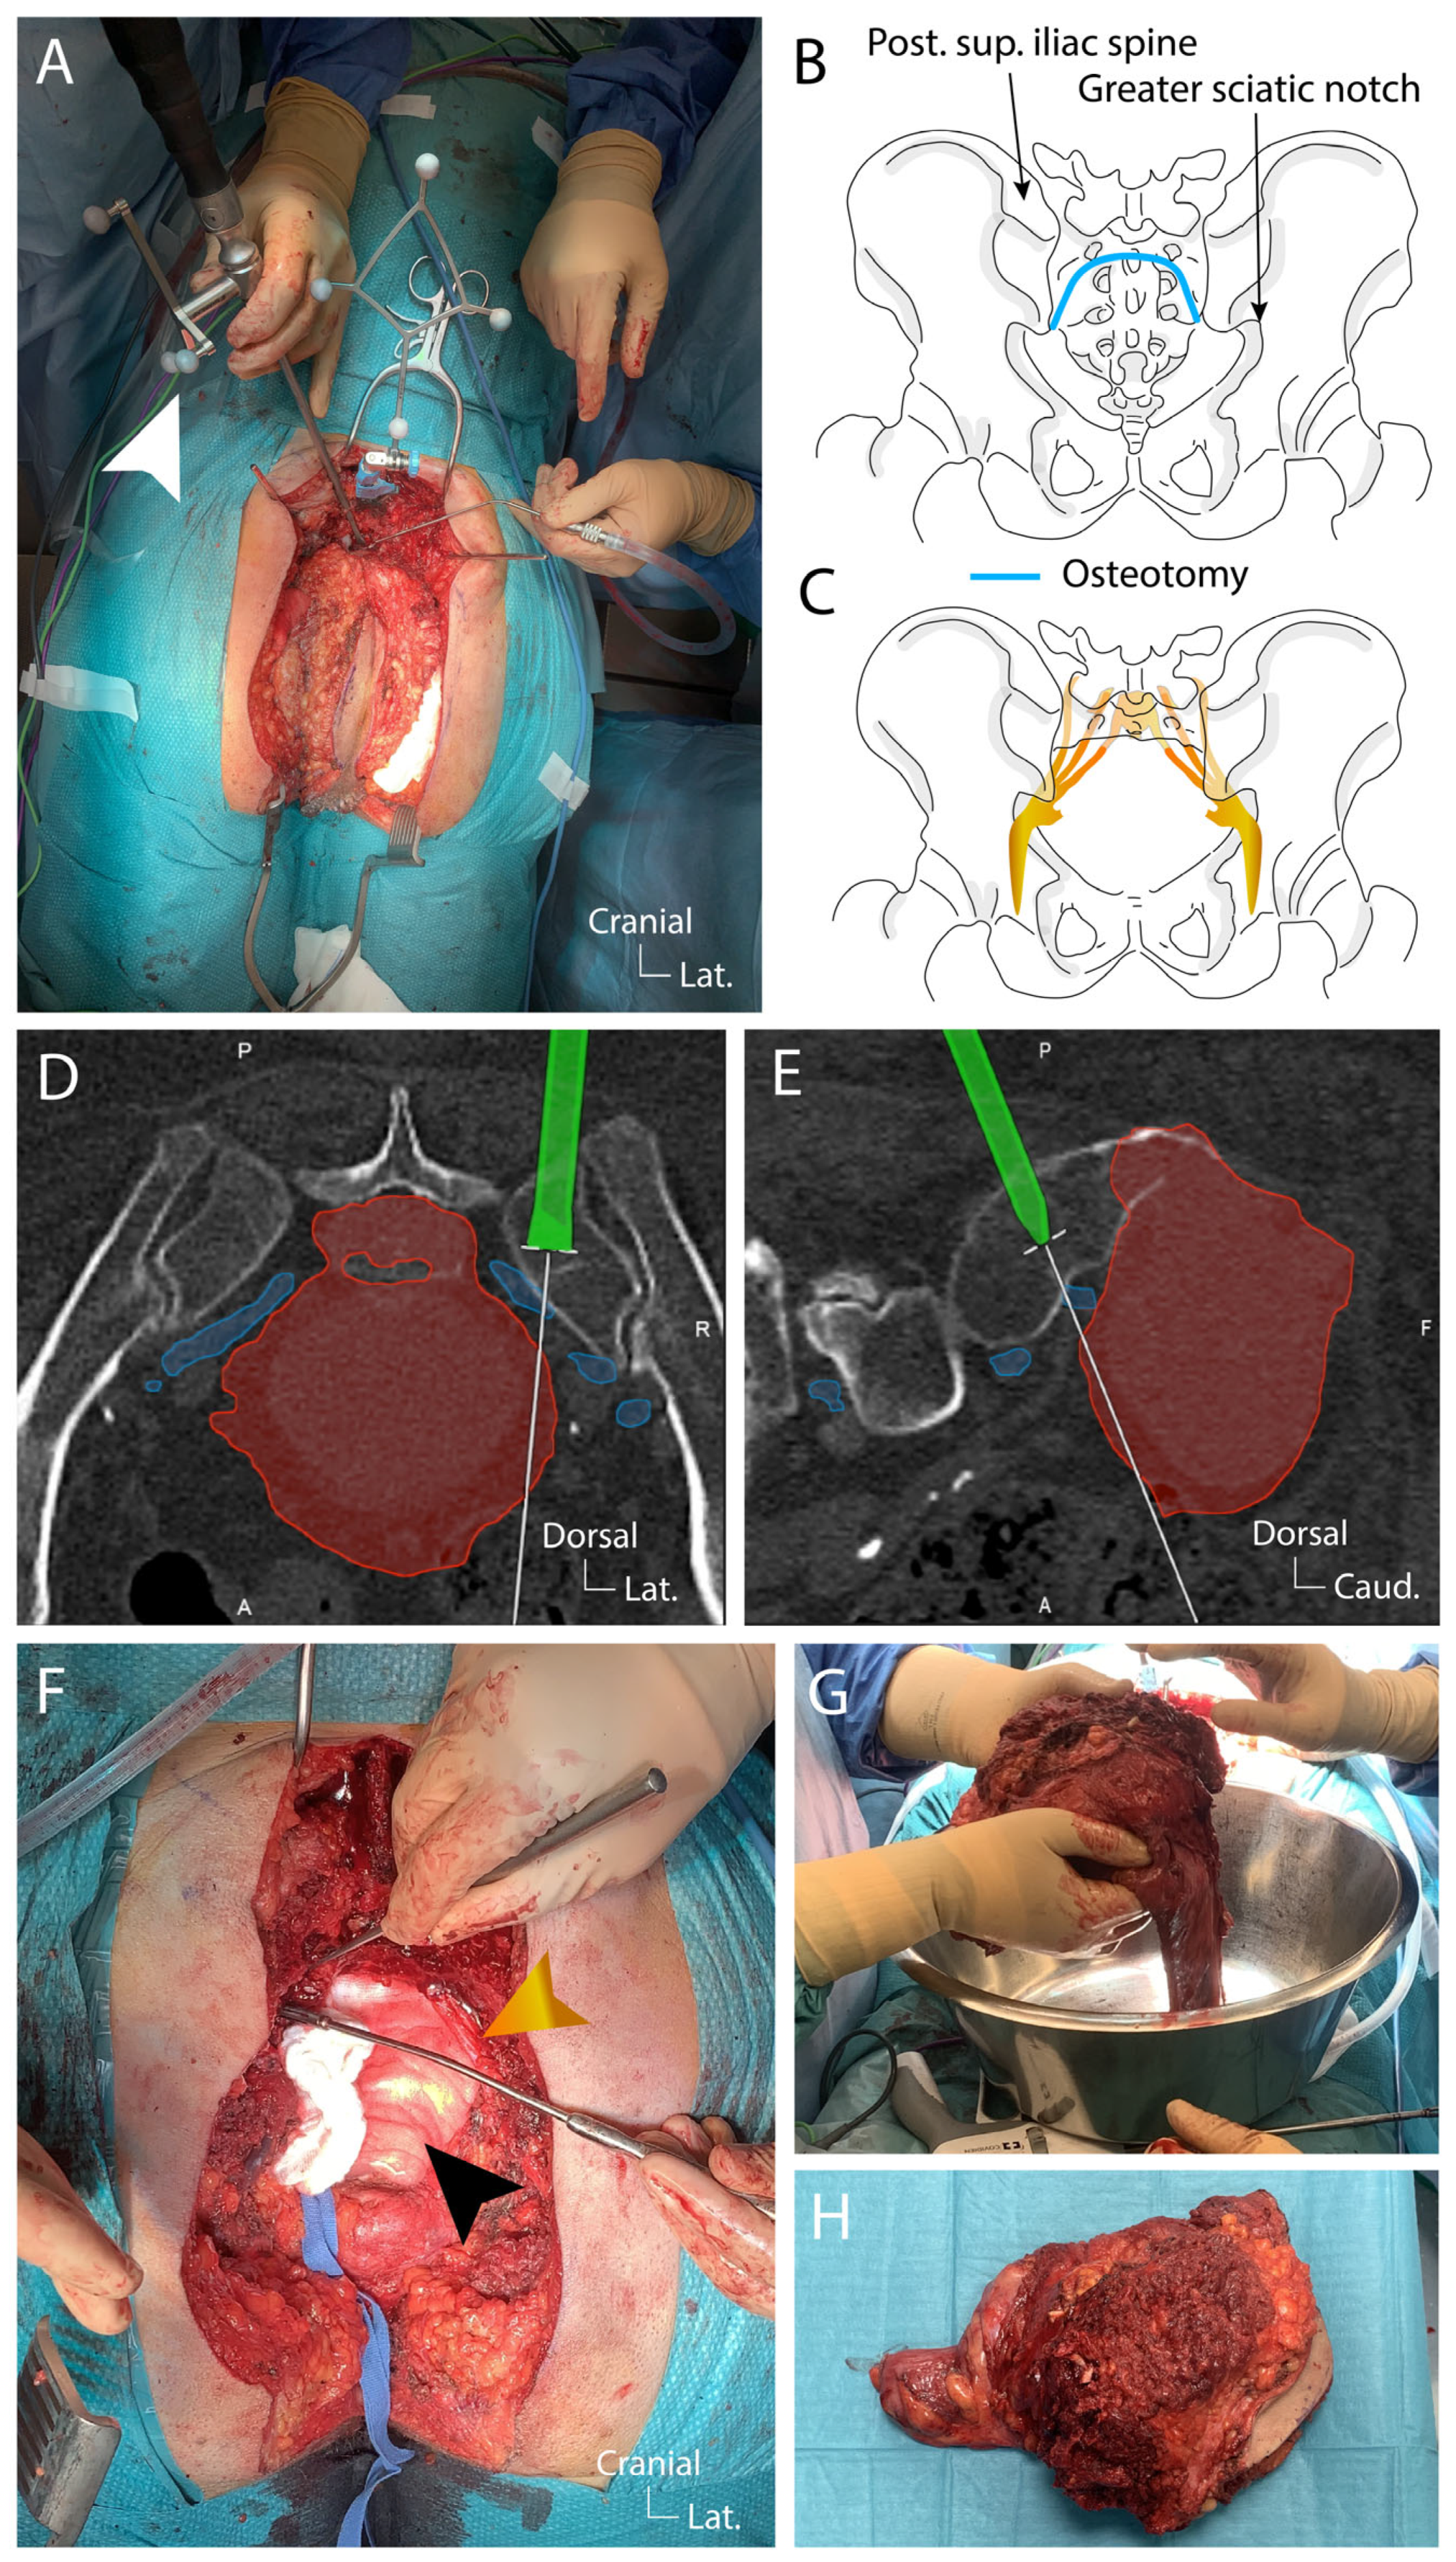

4.2. Preoperative Planning